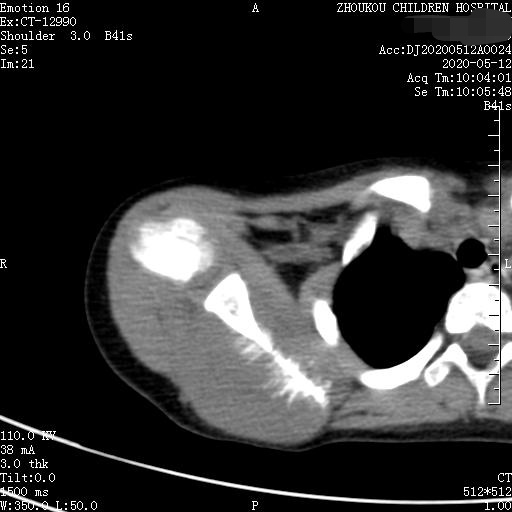

3岁女童以突发右侧肩胛部肿物来院检查,病人无发热、感冒症状,拍右肩关节正位片示:右侧肩关节肩胛岗上缘骨质密度欠均匀,建议CT进一步检查。

通过CT平扫发现:右侧肩胛骨骨质密度不均,骨质内可见“虫食样”低密度影,骨质边缘可见多发放射状骨针,呈“日光射线征”。周围软组织明显肿胀,肌间隙模糊。CT检查意见:考虑:右肩胛骨占位,骨肉瘤可能,不除外其它恶性肿瘤病变,请结合临床及相关检查注意复查。 影像鉴别诊断:骨肉瘤是指起源于骨间叶组织,遗留形成骨细胞直接形成骨样组织为特征的恶性肿瘤,是比较常见的骨恶性肿瘤,好发于十到二十岁青少年,骨肉瘤常见于管状骨,股骨远端胫骨近端最多见,表现为疼痛局部肿胀运动障碍,实验室检查都有碱性磷酸酶升高。